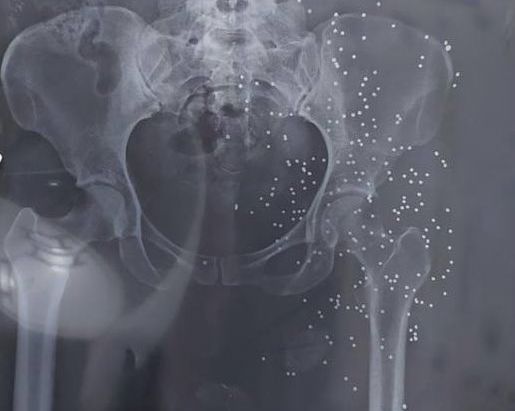

In addition to photos and videos of the injuries, the batch includes dozens of x-ray images and CT scans of pellets and slugs in the head, neck, chest and legs of the protestors. The Islamic Republic has killed many protesters with rubber bullets and metal pellets and blinded so many others.

The regime’s security forces have been extensively using cartridges of shotshell loaded with numerous small balls or birdshots, or medium-sized buckshots as well as single large solid projectiles known as a slug to quash the nationwide protests, ignited by the death in custody of 22-year-old Mahsa Amini in September 2022.